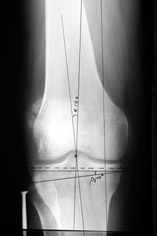

Отправитель: T. Derek V. Cooke 13 Сентябрь 2005, 23:51

|

Hello Alex:

Thanks for the clinical photo.

Your patient appears to have "Insquinting Knees"?

I am attaching a word doc with a 'print screen' of the program in use, showing the images being viewed and analysed

. On the right leg you can see some of the tools (from the tool bar above) applied to demonstrate a mild mech-axis varus of about 5 degrees.

On the left the bone landmarks used in the anlaysis are shown.

The data for the analysis are in the XLs sheet below, exported from the program automatically.

I have given a label of the abreviations and some normative values.

In essence she has a mild mech-axis varus of 7 degrees with some contribution from the femur (2) degrees and more from the tibia (6 degrees), none from the joint.

The analysis took about 6 mins.

Regards

Derek

TDVC> In essence she has a mild mech-axis varus of 7 degrees

TDVC> with some contribution from the femur (2) degrees and more from

TDVC> the tibia (6 degrees), none from the joint.

And what is conclusion? Should it be corrected, by what means, at what level, to what axis, with what lateral/medial translation?